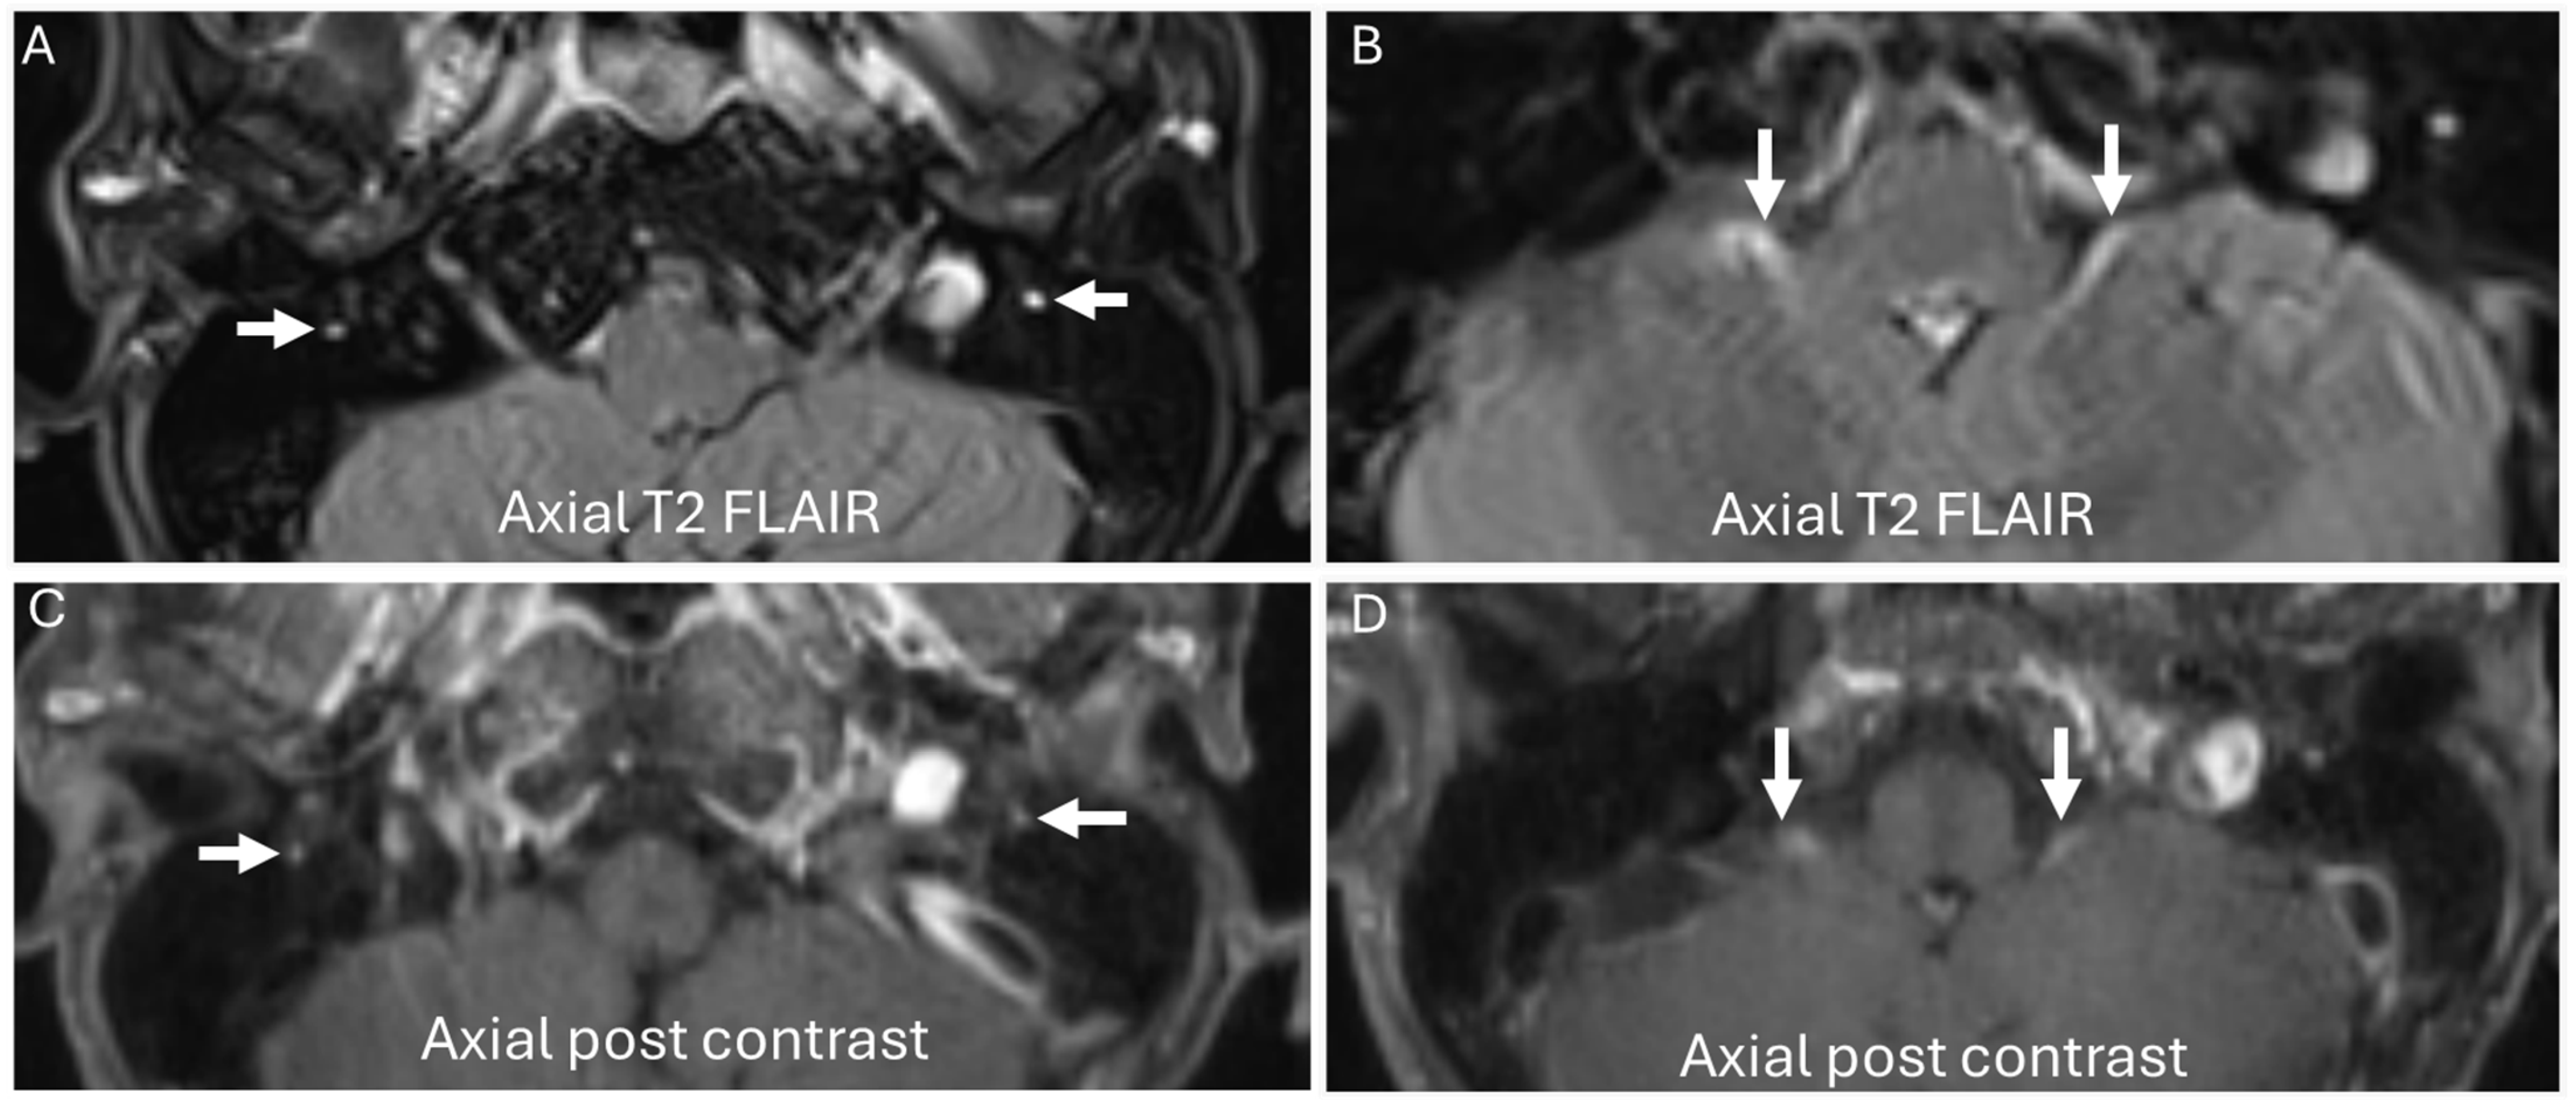

3.4. Chronic Ataxic Neuropathy, Ophthalmoplegia, IgM Paraprotein, Cold Agglutinins, and Disialosyl Antibodies (CANOMAD)

| CANOMAD |

|